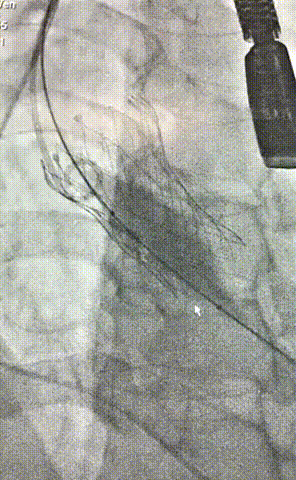

2.主动脉根部造影,瓣上钙化清晰,未见明显反流影;

3.直头导丝跨瓣,通过交换导丝将猪尾导管引入左室,测得跨瓣压差约60mmHg;

4.180次/分快速起搏下以25mm TaurusAtlas球囊进行预扩张,扩张同时造影无明显腰征,无造影剂渗漏,双侧冠脉显影清晰;

5.根据术前评估及球囊预扩情况,选择31mm沛嘉TaurusElite瓣膜进行植入;

7.瓣膜形态良好,未见明显形态改变,遂予以完全释放;

8.即时超声评估提示存在少量瓣周漏,峰值跨瓣压差约10mmHg经术中讨论认为瓣上限制性结构压缩为瓣周漏主因,遂予以球囊后扩;

9.后扩完毕,造影示微量瓣周漏,瓣膜形态良好,手术圆满成功!